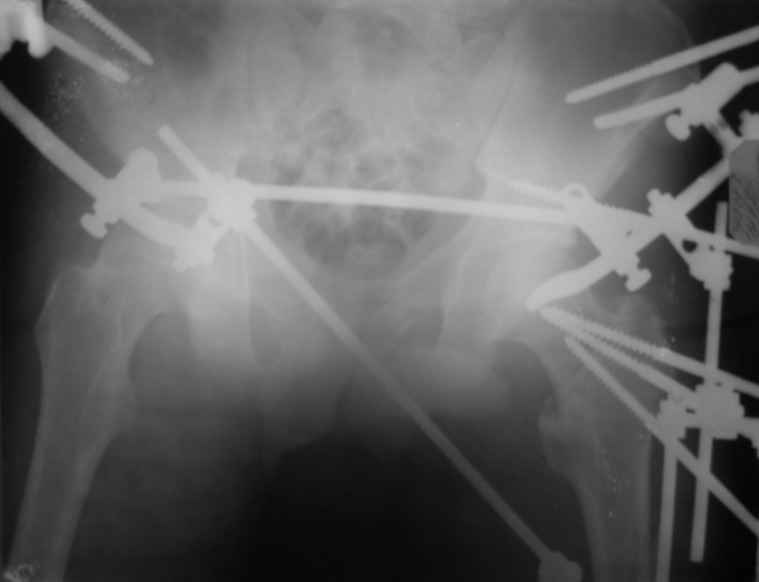

Вот снимки по свежей ситуации, парень 19 лет, длинный оскольчатый перелом бедра от шейки до в-с/3. давно уже ходит на своих ногах.

Представленные Вами рентгенограммы действительно являются примером качественной фиксации спице-стержневым аппаратом. Они, как ни что другое, многое иллюстрируют.

Компоновку данного аппарата, в котором дистальный отломок фиксирован лишь на дистальном уровне, а проксимальный вообще сам по себе никак, только через бывший сустав, назвать стабильной никак нельзя. Нет стабильности - нет нормального заживления, но есть осложнения, надеюсь, это-то можно экстраполировать на вашего больного?

Опять же, раз сустав потерян, то открывается свобода ввести дополнительно стержень в тазовой подсистеме хоть через шейку-головку-вертлужку. Либо всё-таки над суставом. А ввести его надо, весьма заметно добавляет стабильности. Так делаем не только мы, видел снимки в Кургане.